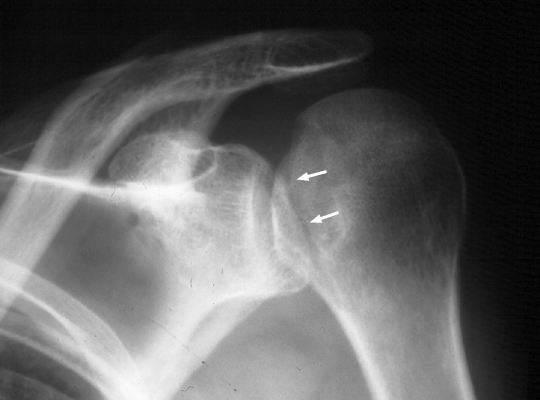

Diagnosis:Posterior shoulder dislocation Discussion:Trough line is seen with posterior shoulder dislocation. When the humeral head is forced posteriorly in internal rotation, the anterior aspect of the humeral head is driven against the posterior glenoid rim. With sufficient force, the head will sustain a compression fracture. In many cases of posterior dislocation of the shoulder, two parallel lines of cortical bone can be seen. The outer (more medial) cortical line represent the medial cortex of the humeral head, while the other line represents the margin of a "trough" like impaction fracture. References: